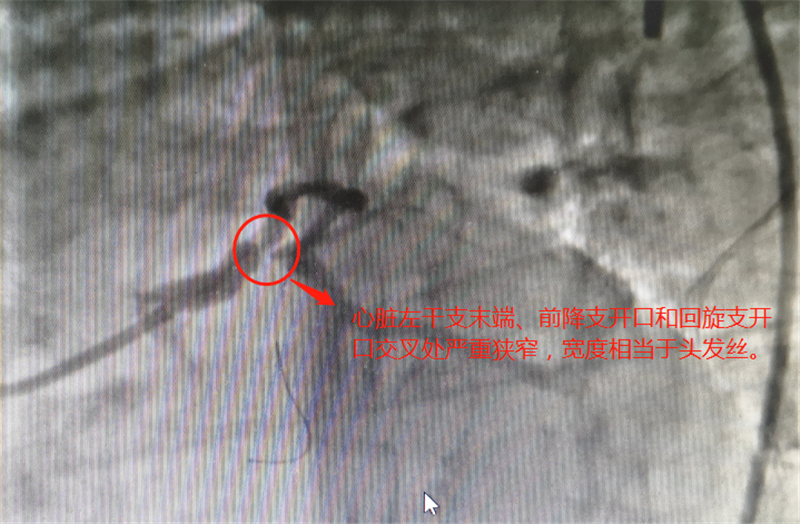

细如发丝,心细如丝丨心血管分叉狭窄细如发丝,介入团队心细如丝,省级专家点赞!

“患者有冠状动脉粥样硬化性心脏病,其中右冠状动脉完全堵死,左主干末端、前降支开口以及回旋支开口均为次全闭塞,只能过一丝丝血流。”3月30日,三水区人民医院DSA介入中心内,心血管内科主任李晚泉主任医师通过远程视频会诊的方式与名医工作室省级专...